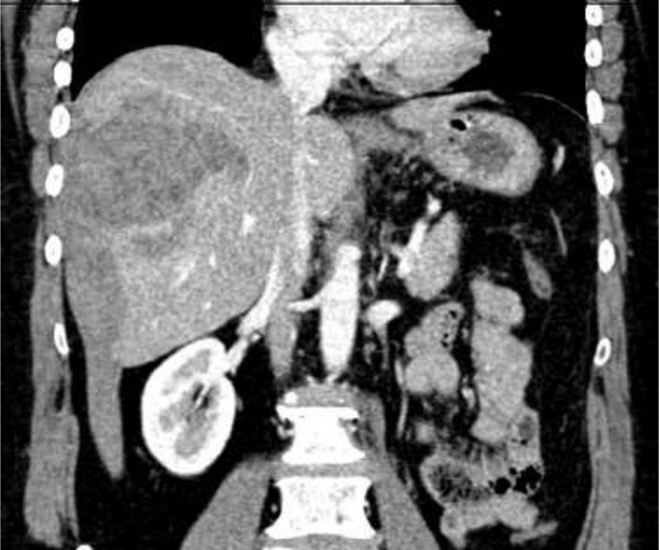

ACDC, 38 anos, sexo feminino, dá entrada no serviço de urgência, com quadro de dor abdominal em hipocôndrio direito que irradia para as costas, de forte intensidade, sudorese e taquicardia. Foi solicitada uma ultrassonografia, e, durante o exame, o radiologista optou por complementar com uma tomografia com contraste, com o seguinte achado:

Enunciado 3531513-1

Qual a principal hipótese diagnóstica para o quadro em questão?